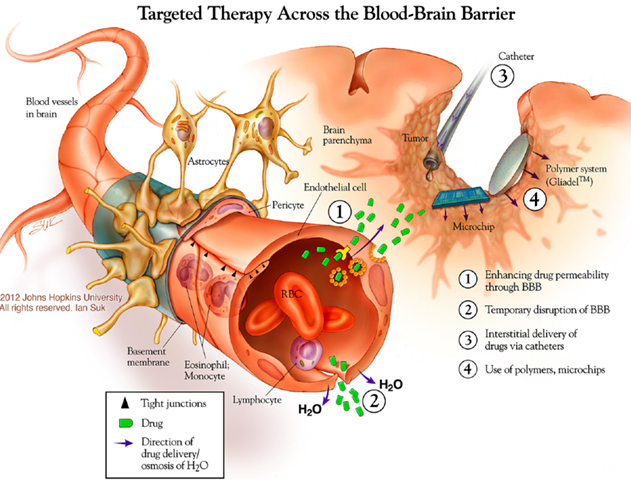

55 brain levels of thought

58 brain Septum attacks on Sept 11,2001